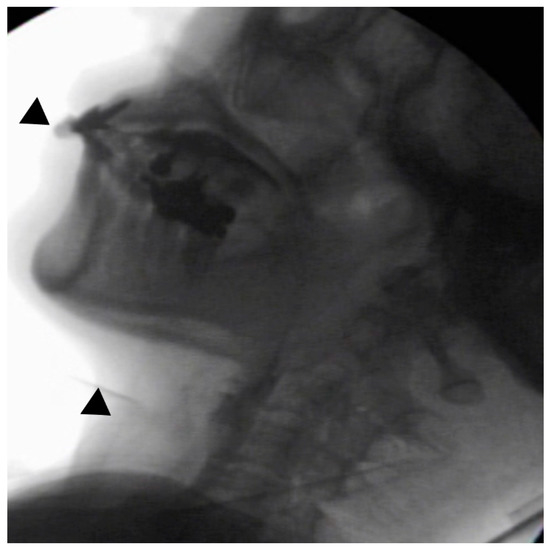

In the seated position, spoon-feeding was infeasible and bolus transport did not occur; furthermore, anterior–posterior tongue movement caused most of the food to dribble out of her mouth. After placing food on top of her tongue using a tube-fitted syringe, most still dribbled out of her mouth (Figure 1a); however, a proportion was transported into the pharynx (Figure 1b). Furthermore, after placing food at the back of her tongue with the patient reclined at 30°, a small amount still dribbled out of her mouth; however, the patient could swallow without aspiration (Figure 2). After increasing the amount placed in her mouth at one time to 7 mL, more food dribbled out of her mouth (Figure 3); additionally, there was a decreased amount transported to the pharynx. When 5 mL of a moderately thick paste was placed in her mouth, none of it dribbled out; however, slight silent aspiration was present (Figure 4). There were no particular issues observed due to peristalsis from the upper esophagus to the stomach.

Figure 3.

The patient was reclined at 30° for the administration of 7 mL of an extremely thick paste. Even when the food was placed in the retromolar area, most of the food dribbled out of her mouth (▲) upon triggering her swallowing reflex.